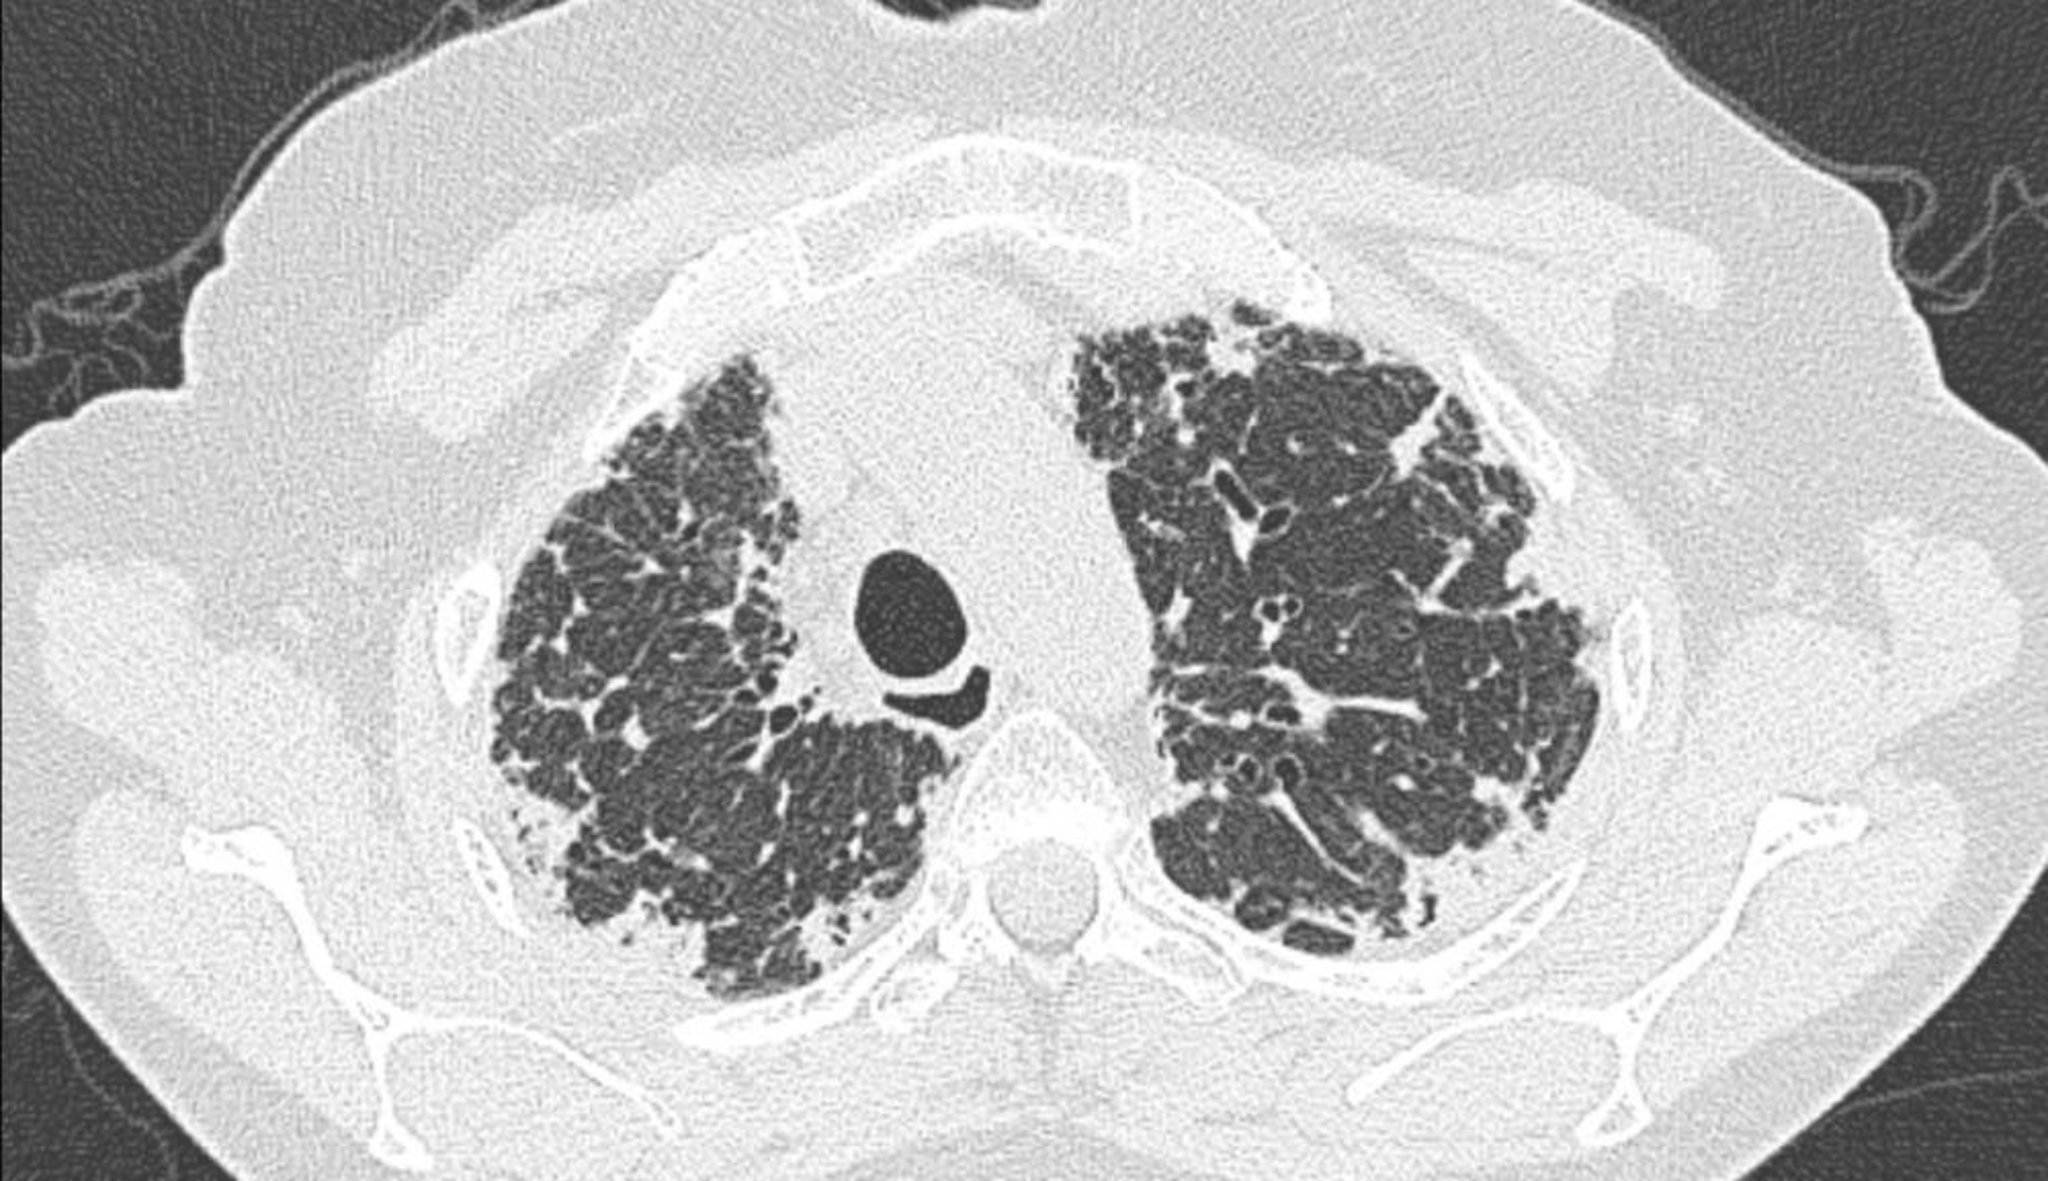

U nguyên bào sợi mô màng phổi tự phát (chụp CT)

Chụp CT ngực cho thấy dày màng phổi và dưới màng phổi.

Hình ảnh do bác sĩ Joyce S. Lee cung cấp